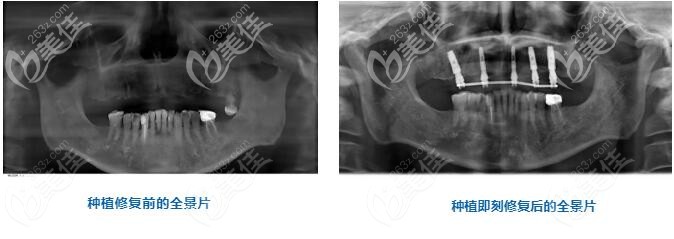

術(shù)后即刻全景片的對比能直觀的看出來,上半口缺失的牙齒已經(jīng)被種植體所取代。